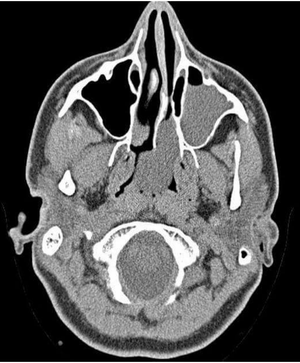

Antrochoanal Polyp arising from mucosa of maxillary sinus, growing backward to choana and nasopharynx. Lead to unilateral nasal obstruction